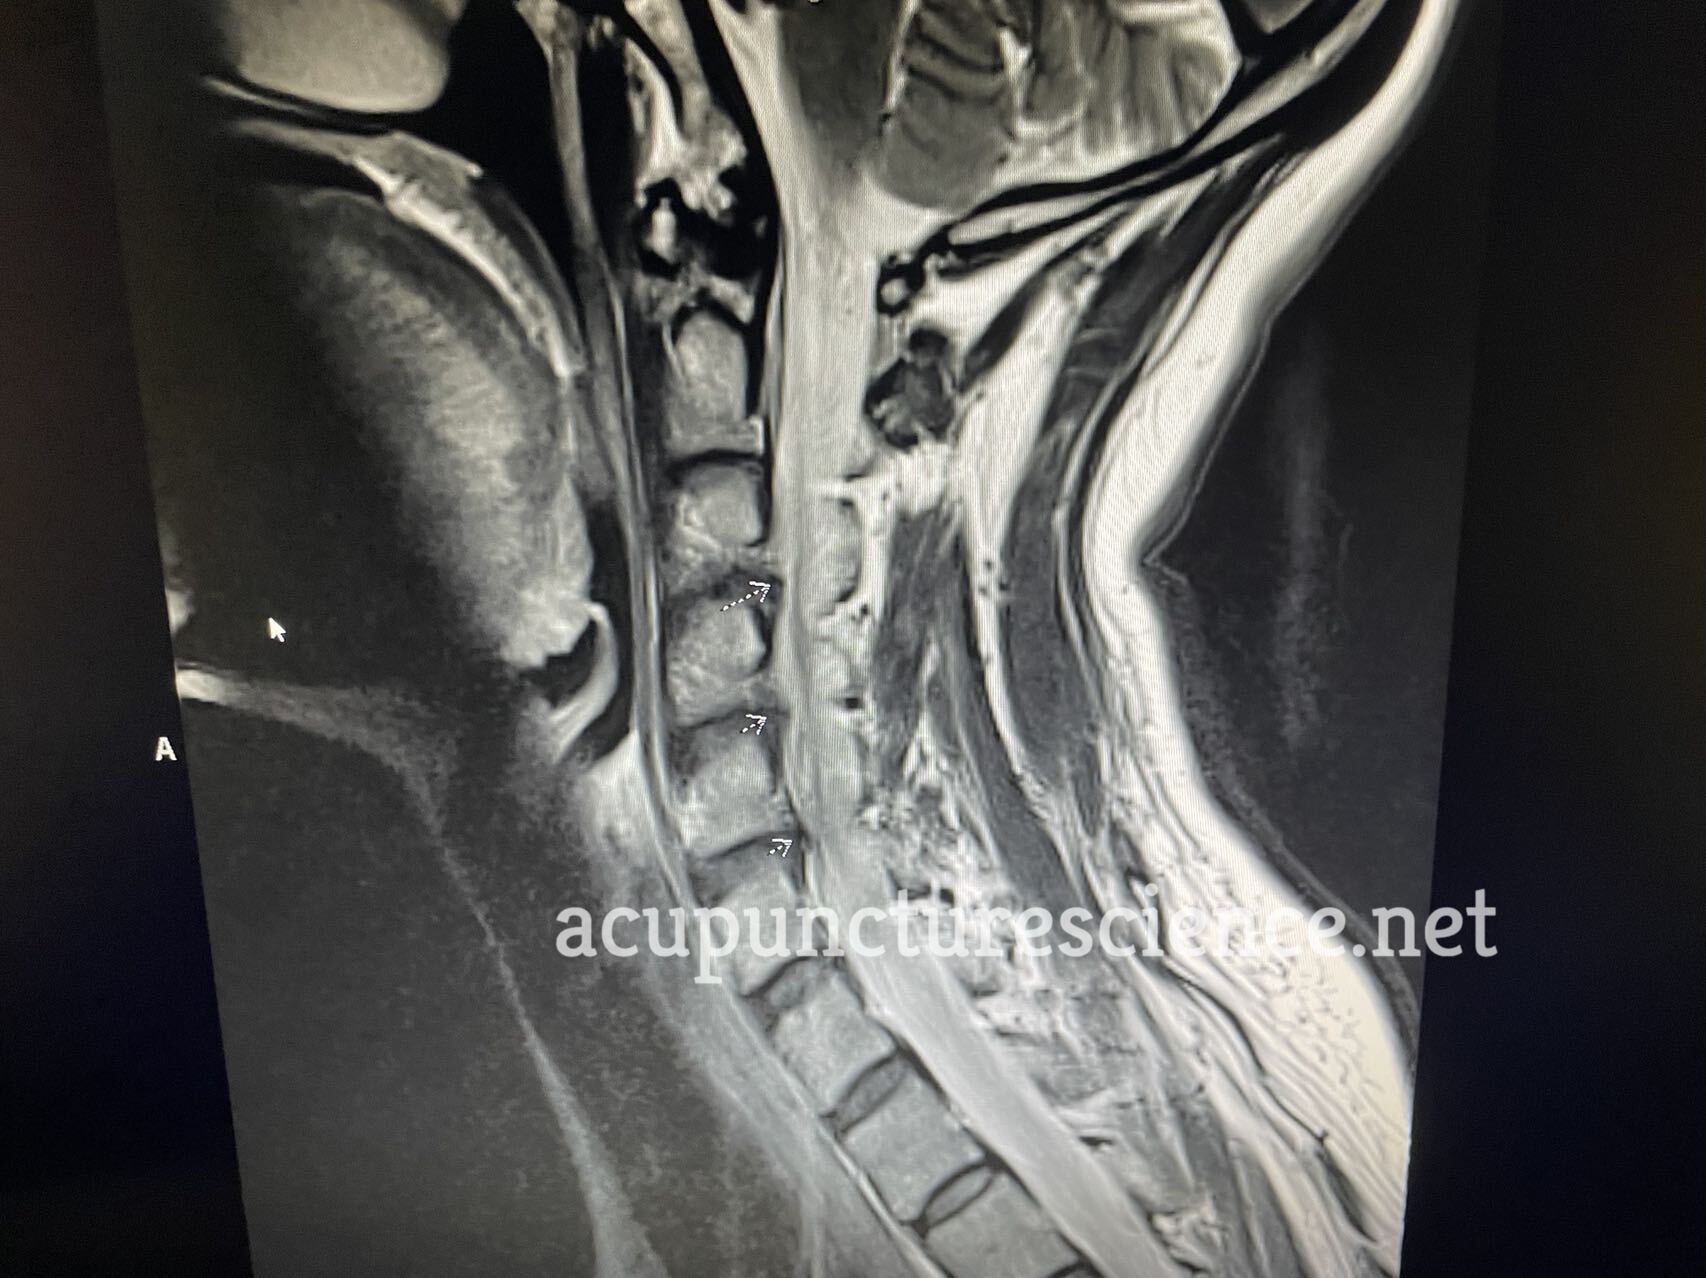

MRI IMPRESSION:

1. Multilevel degenerative disc disease with broad-based disc bulges at C3-C4

through C5-C6 with moderate right neuroforaminal narrowing at C3-C4 and C5-C6.

SPINAL CORD: Normal.

DISCS: Normal.

BONES: Vertebral body height and alignment are normal. Marrow signal is normal.

SOFT TISSUES: Normal.

C2-C3: No canal or foraminal stenosis.

C3-C4: Broad-based disc osteophyte complex is seen with moderate right and mild

left neuroforaminal narrowing. No central canal stenosis.

C4-C5: Broad-based disc osteophyte complex is seen without significant

neuroforaminal narrowing. No central canal stenosis.

C5-C6: Broad-based disc osteophyte complex is seen with moderate right and mild

C6-C7: No canal or foraminal stenosis.

C7-T1: No canal or foraminal stenosis.

OTHER: Visualized posterior fossa is normal.